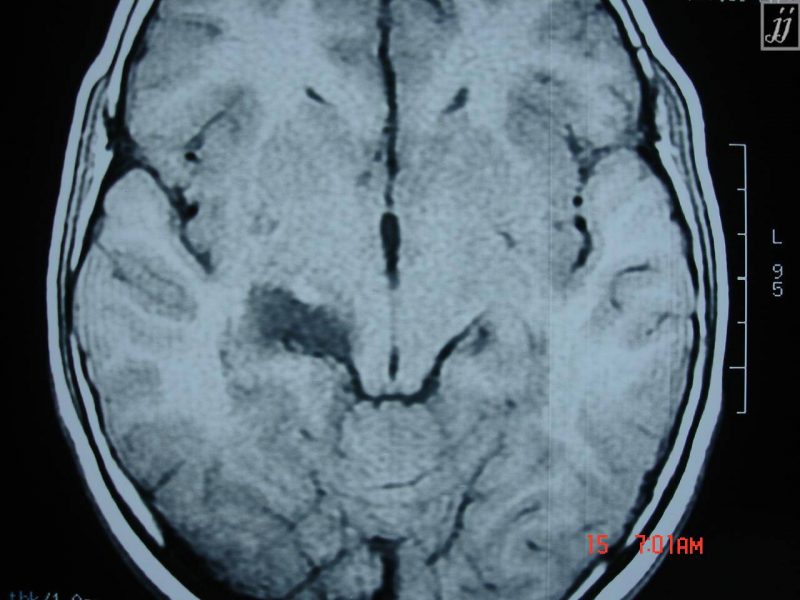

- تشخیص کیست های آراکنوئید به کمک سی تی اسکن یا ام آر آی امکان پذیر است.

تشخیص کیست آراکنوئید

سی تی اسکن و ام آر آی به پزشک جراح در مشخص کردن محل کیست و ویژگی های آن کمک می کنند. در نهایت بهترین روش درمانی برای کودک بر اساس نتایج آزمایشات مشخص می شود.